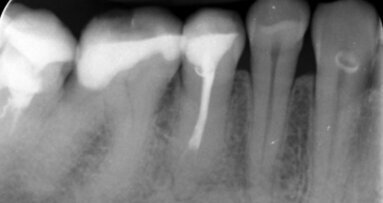

Przedstawiono obraz kliniczny wyjściowy 47-letniej pacjentki ze zdiagnozowaną zaawansowaną uogólnioną chorobą przyzębia, licznymi brakami zębowymi, brakiem protetycznego uzupełnienia zębów bocznych, zmianami okołowierzchołkowymi, niepełnym leczeniem endodontycznym. Pacjentka wymagająca kompleksowego leczenia stomatologicznego. Aby stworzyć wyjściowy plan leczenia, konieczne jest wdrożenie leczenia wstępnego (faza higienizacyjna), aby sprawdzić motywację pacjentki do dalszego leczenia wysokospecjalistycznego i ocenić rokowanie zębów.

Po higienizacji stan kliniczny pacjentki poprawił się. Wykonano kontrolne badania obrazujące zaawansowanie choroby przyzębia.

Następnie zastosowano laser Nd:YAG do sterylizacji kieszeni przyzębnych, dekontaminacji (Ryc. 3-7) i laser Er:YAG do usunięcia kamienia poddziąsłowego (Ryc. 8-12) oraz ponownie laser Nd:YAG do stabilizacji skrzepu (Ryc. 13 i 14). Na rycinie 15 przedstawiono stan bezpośrednio po zabiegu usunięcia kamienia poddziąsłowego laserem Er:YAG wraz ze sterylizacją kieszeni przyzębnych laserem Nd:YAG (LightWalker, Fotona).